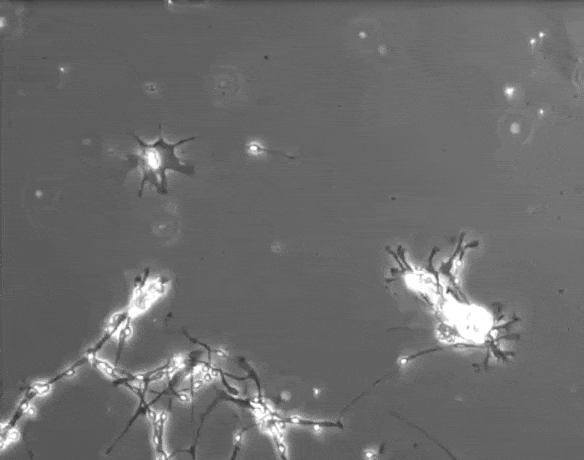

1. Нервові клітини не тільки гинуть, але і постійно відновлюються, утворюючи все нові зв'язки

Всупереч відомому думку, нейрони не здатні гинути від стресу або перевантаження. Зазвичай вони гинуть від дефіциту поживних речовин, накопичення токсинів і нестачі кисню. Всьому цьому сприяють ліки, міцну каву і чай, тютюн, алкоголь, надмірні фізичні навантаження і хвороби. Як говорять учені, щоб зберегти нейрони, досить вчитися чомусь новому і проводити більше часу з близькими.